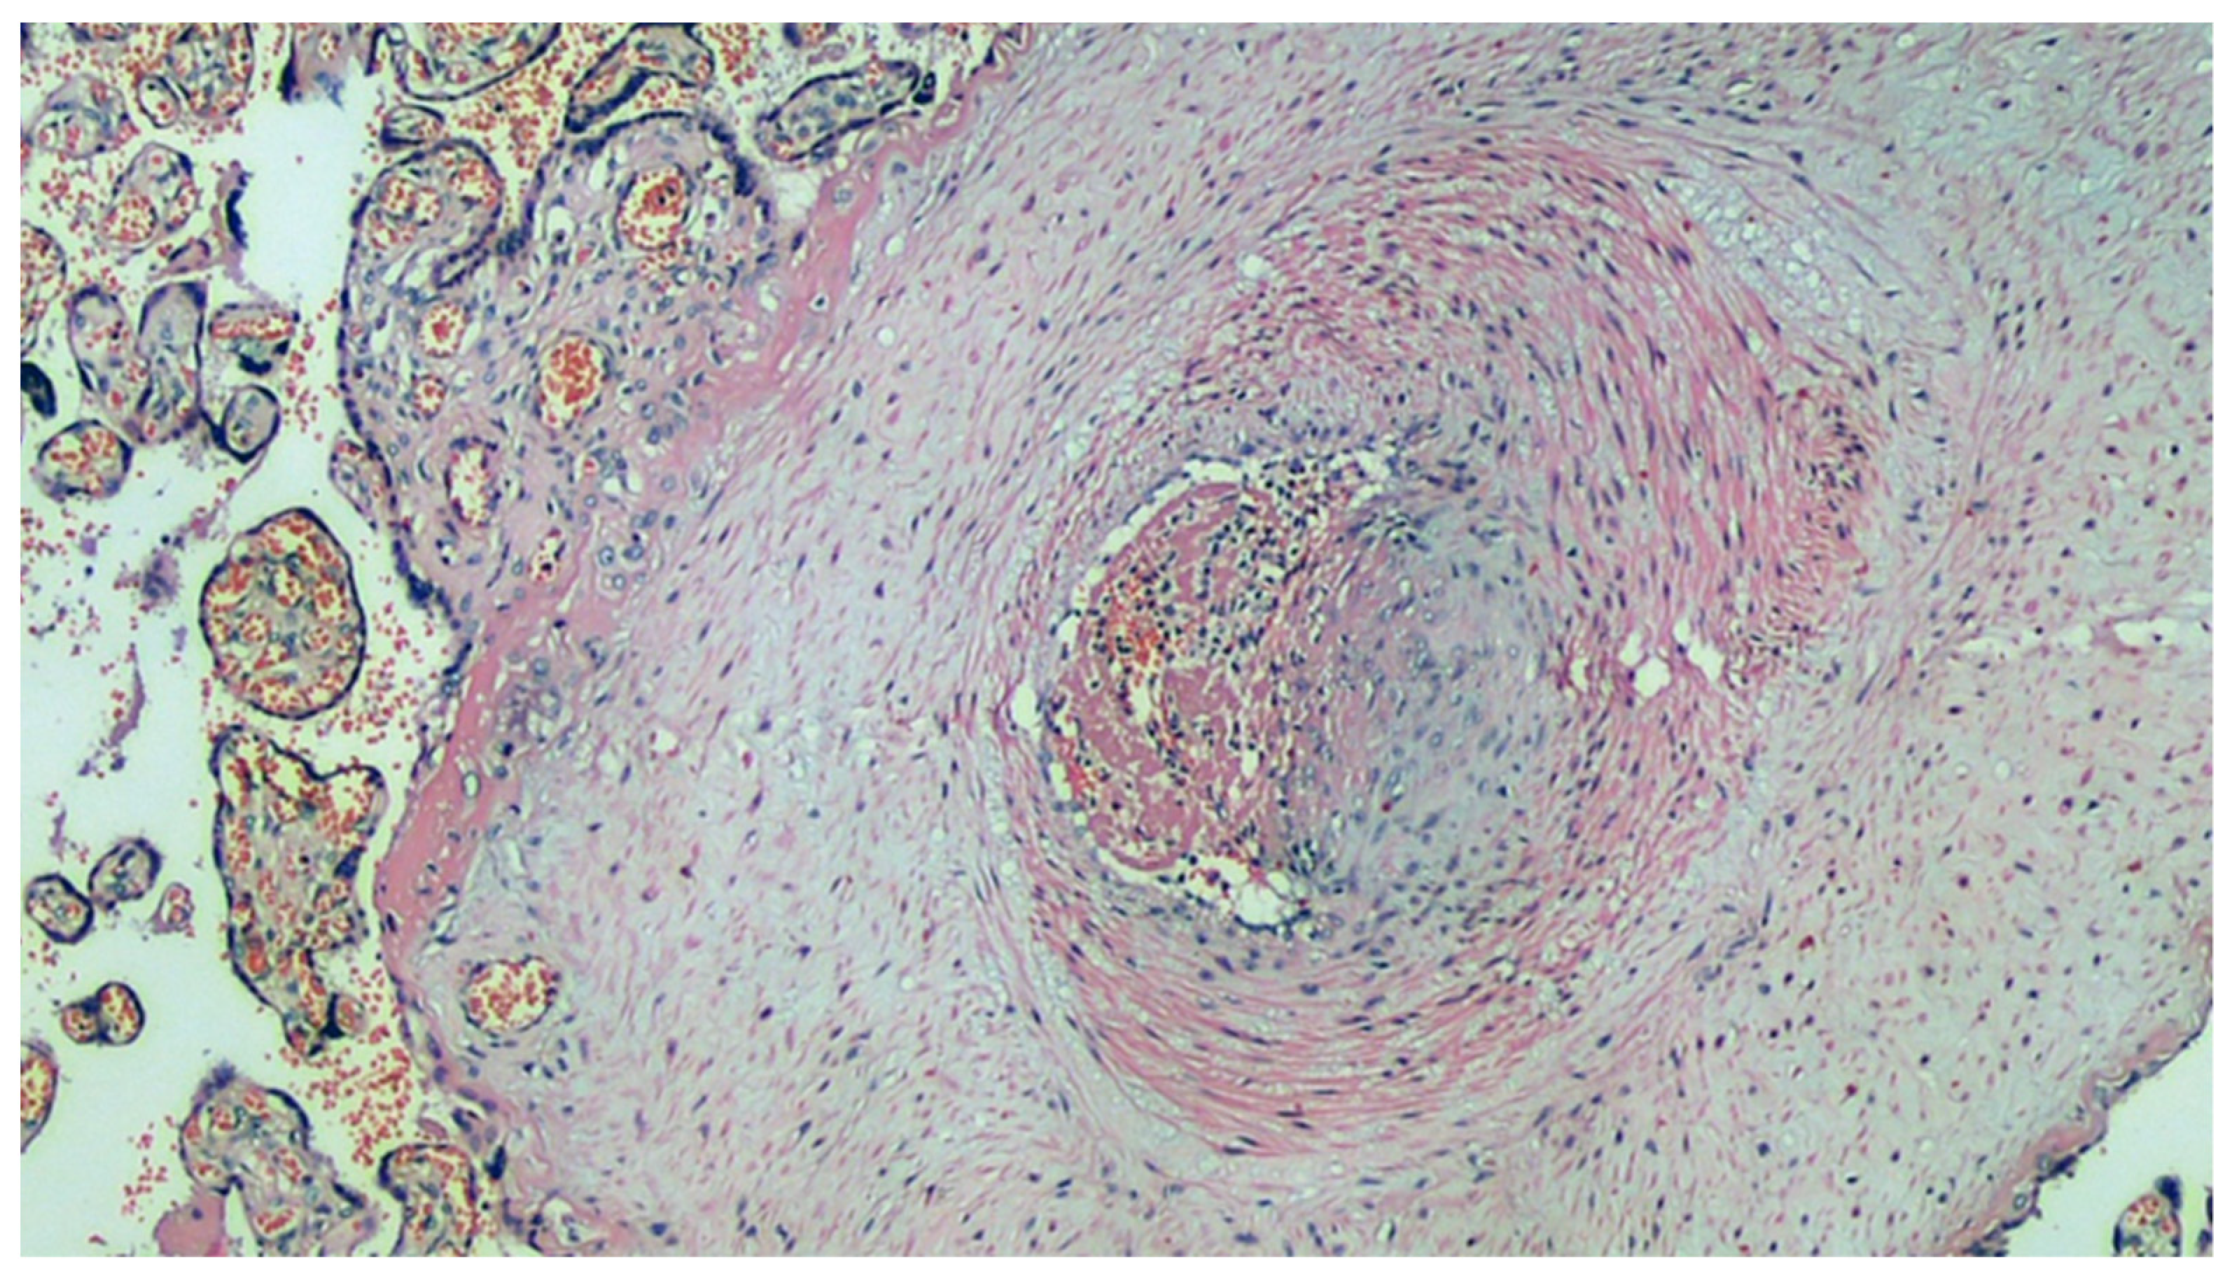

Figure 5.

Histological section of the main villus: the artery has a thickened muscular wall, marked intimal fibrous thickening (probable organization of arterial thrombus), clear reduction of the lumen, and recent thrombosis of the residual lumen. H&E, 200×.